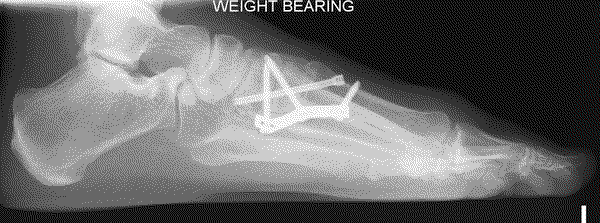

Lapidus (metatarsal cuneiform fusion)

This involves a fusion of the first metatarsal cuneiform joint, allowing the first metatarsal to be rotated back into a straight position. It is normally reserved for severe deformities. Once the corrected position has been obtained it is usually maintained with a plate and screws.

Due to the corrective power of this procedure, there is a risk of overcorrection of the bunion, which may result in poor alignment with associated pain and arthritis in the big toe joint. A failure of the two bones to unite (non-union) can result in poor alignment and pain. In our department the audited risk of a non-union is 2%, which is lower than the average reported rate of 3.8%. A non-union may require revision surgery.